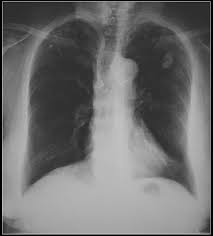

X Ray Showing A Frontal View Of The Chest Of A 54 Year Old Female The X Ray Shows A Calcified Left Hilar Lymph Node Which Most Likely Resulted From Prior Granulomatous Disease Also